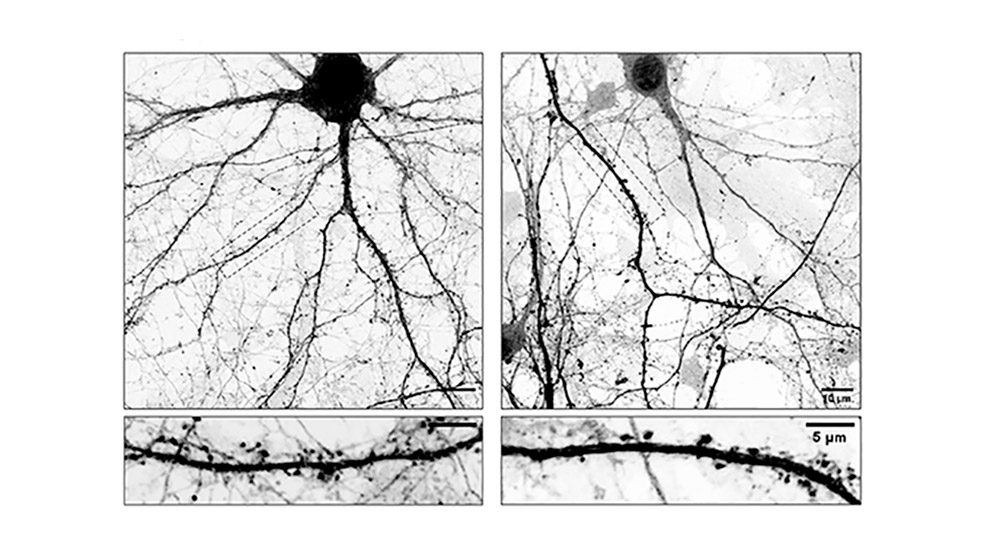

A través de diversos ensayos los equipos científicos descubrieron que L-Dopa puede incorporarse a los microtúbulos que forman parte del esqueleto interno de las neuronas. Estos microtúbulos funcionan como “rieles” microscópicos que permiten el movimiento interno de sustancias esenciales y tienen un papel crucial en el mantenimiento de la conexión entre las neuronas (sinapsis). “El problema es que cuando L-Dopa se integra en estos microtúbulos los hace menos dinámicos afectando su ingreso a las espinas dendríticas, estructuras que funcionan como las ‘antenas’ receptoras de la neurona donde se forman las sinapsis. Como consecuencia directa de esto, las neuronas comienzan a perder espinas, claves para la comunicación neuronal. Entendemos que esta inestabilidad sináptica podría explicar algunas de las complicaciones que aparecen luego de un tiempo prolongado de tomar L-Dopa”, señala Gastón Bisig, investigador del CONICET en el CIQUIBIC y uno de los líderes del estudio.

Para poder comprobar esta hipótesis, los investigadores utilizaron como modelo de estudio cultivos primarios de neuronas; células nerviosas que se obtienen de una región específica del cerebro de un ratón y que se cultivan en el laboratorio bajo condiciones controladas que les permiten madurar y desarrollarse como lo harían en el cerebro. Estas células fueron tratadas con L-Dopa y mediante microscopios de alta resolución se analizó cómo cambiaba la forma y la cantidad de espinas dendríticas. En el marco de estos experimentos, también realizaron tinciones específicas con moléculas fluorescentes que les permitieron visualizar estructuras internas de las células. Así pudieron ver en tiempo real la dinámica de los microtúbulos dentro de las neuronas, es decir, cómo los “rieles” crecen, se acortan y se mueven. Además, trabajaron con neuronas modificadas genéticamente que no poseen ciertas enzimas esenciales para que la L-Dopa se incorpore en los microtúbulos; lo que permitió demostrar que los efectos negativos suceden solo cuando esta incorporación realmente ocurre.